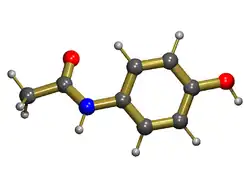

Paracetamol

Paracetamol also known as acetaminophen, and by the brand names of Tylenol and Panadol, is usually well-tolerated in prescribed dose, but overdose is the most common cause of drug-induced liver disease and acute liver failure worldwide.[12] Damage to the liver is not due to the drug itself but to a toxic metabolite (N-acetyl-p-benzoquinone imine (NAPQI)) produced by cytochrome P-450 enzymes in the liver.[13] In normal circumstances, this metabolite is detoxified by conjugating with glutathione in phase 2 reaction. In an overdose, a large amount of NAPQI is generated, which overwhelms the detoxification process and leads to liver cell damage. Nitric oxide also plays a role in inducing toxicity.[14] The risk of liver injury is influenced by several factors including the dose ingested, concurrent alcohol or other drug intake, interval between ingestion and antidote, etc. The dose toxic to the liver is quite variable from person to person and is often thought to be lower in chronic alcoholics.[15][16] Measurement of blood level is important in assessing prognosis, higher levels predicting a worse prognosis. Administration of Acetylcysteine, a precursor of glutathione, can limit the severity of the liver damage by capturing the toxic NAPQI. Those that develop acute liver failure can still recover spontaneously, but may require transplantation if poor prognostic signs such as encephalopathy or coagulopathy is present (see King's College Criteria).[17]